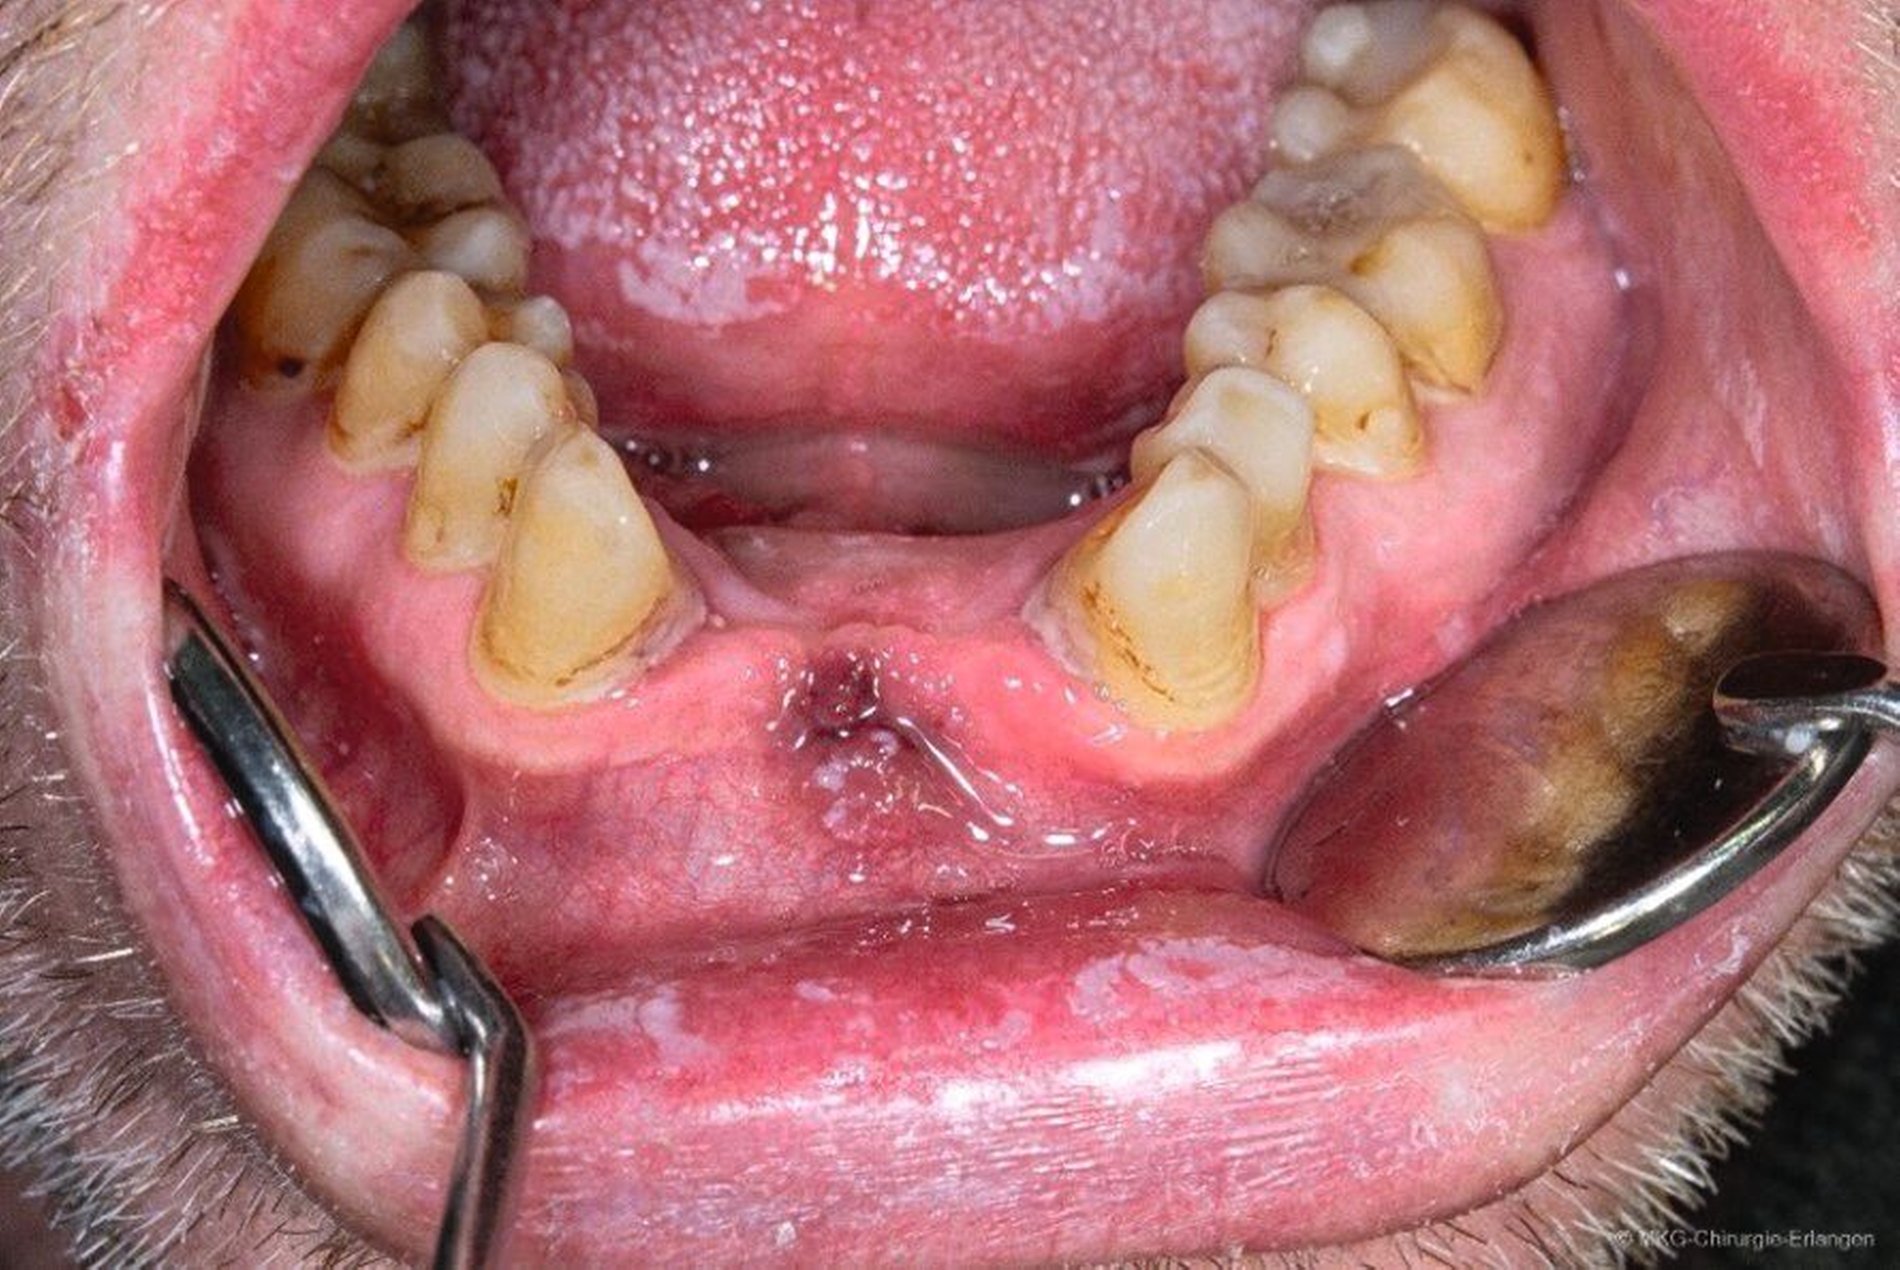

In der klinischen Untersuchung zeigten sich im Bereich des harten und des weichen Gaumens bläulich-livide Verdickungen der Schleimhaut mit einem flächigen Soorbefall, die auf Palpation schmerzhaft waren. Der Übergang in den Rachen war stark gerötet, die restliche Mundschleimhaut von Soor bedeckt. An der linken Unterlippe konnte man einen circa 0,5 cm x 0,5 cm großen bläulichen Knoten erkennen. Die Speicheldrüsenausgänge waren vergrößert und gerötet. Der Patient zeigte eine mäßige Mundhygiene bei einem konservierend versorgten teilbezahnten Gebiss.